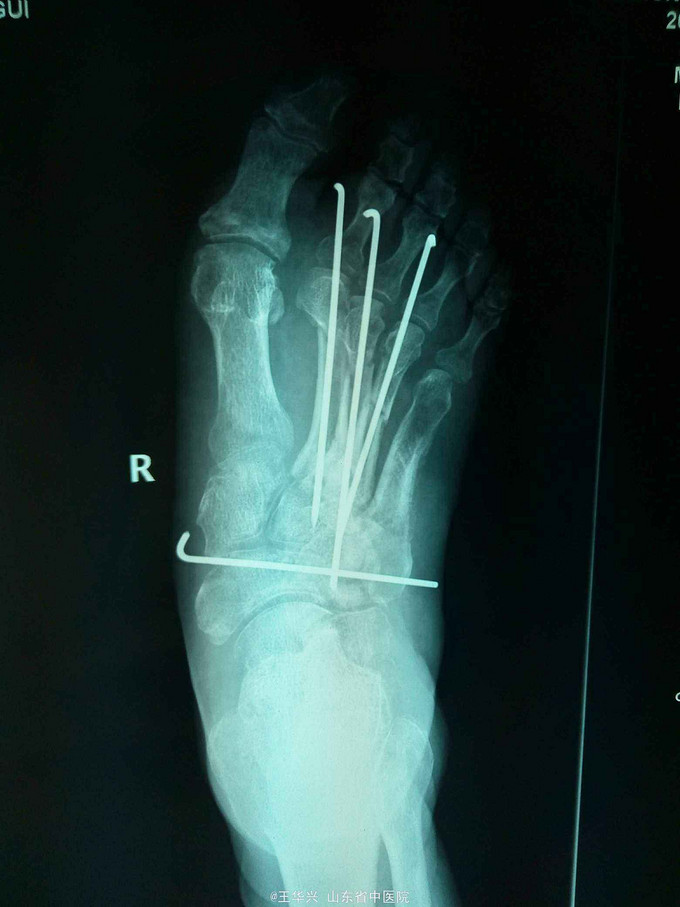

查体:左足疼痛,功能活动受限,伴有大面积软组织损伤,软组织向外侧翻转,足部前侧可见5*3cm软组织缺损,患处麻木感,足背动脉不可及。 辅助检查:x线 左足第2,3,4跖骨骨折

诊断:左足毁损伤 治疗:入院时已达到截肢标准,但患者家属不能接受,遂行常规手术。多次清创,行急症手术,给予简单钛针固定,软组织损伤给予原位缝合。细菌培养结果,万古霉素敏感,万古霉素局部填塞创口换药,术后给予多次清创,清除坏死组织及vsd负压吸引。待左足缺损区软组织条件可,行交腿皮瓣。